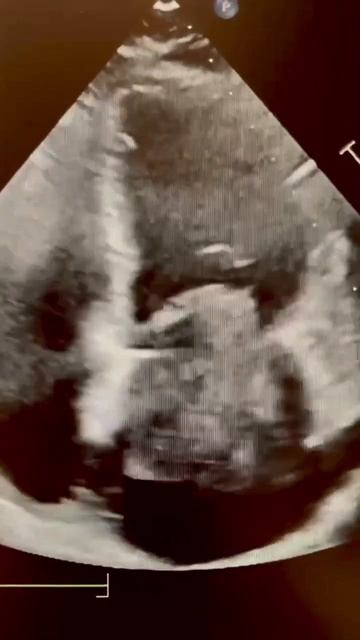

Left Atrial Myxoma echocardiography echocardiogram cardiology

About 70 of atrial myxomas occur in the left atrium. What do you think of this case?,